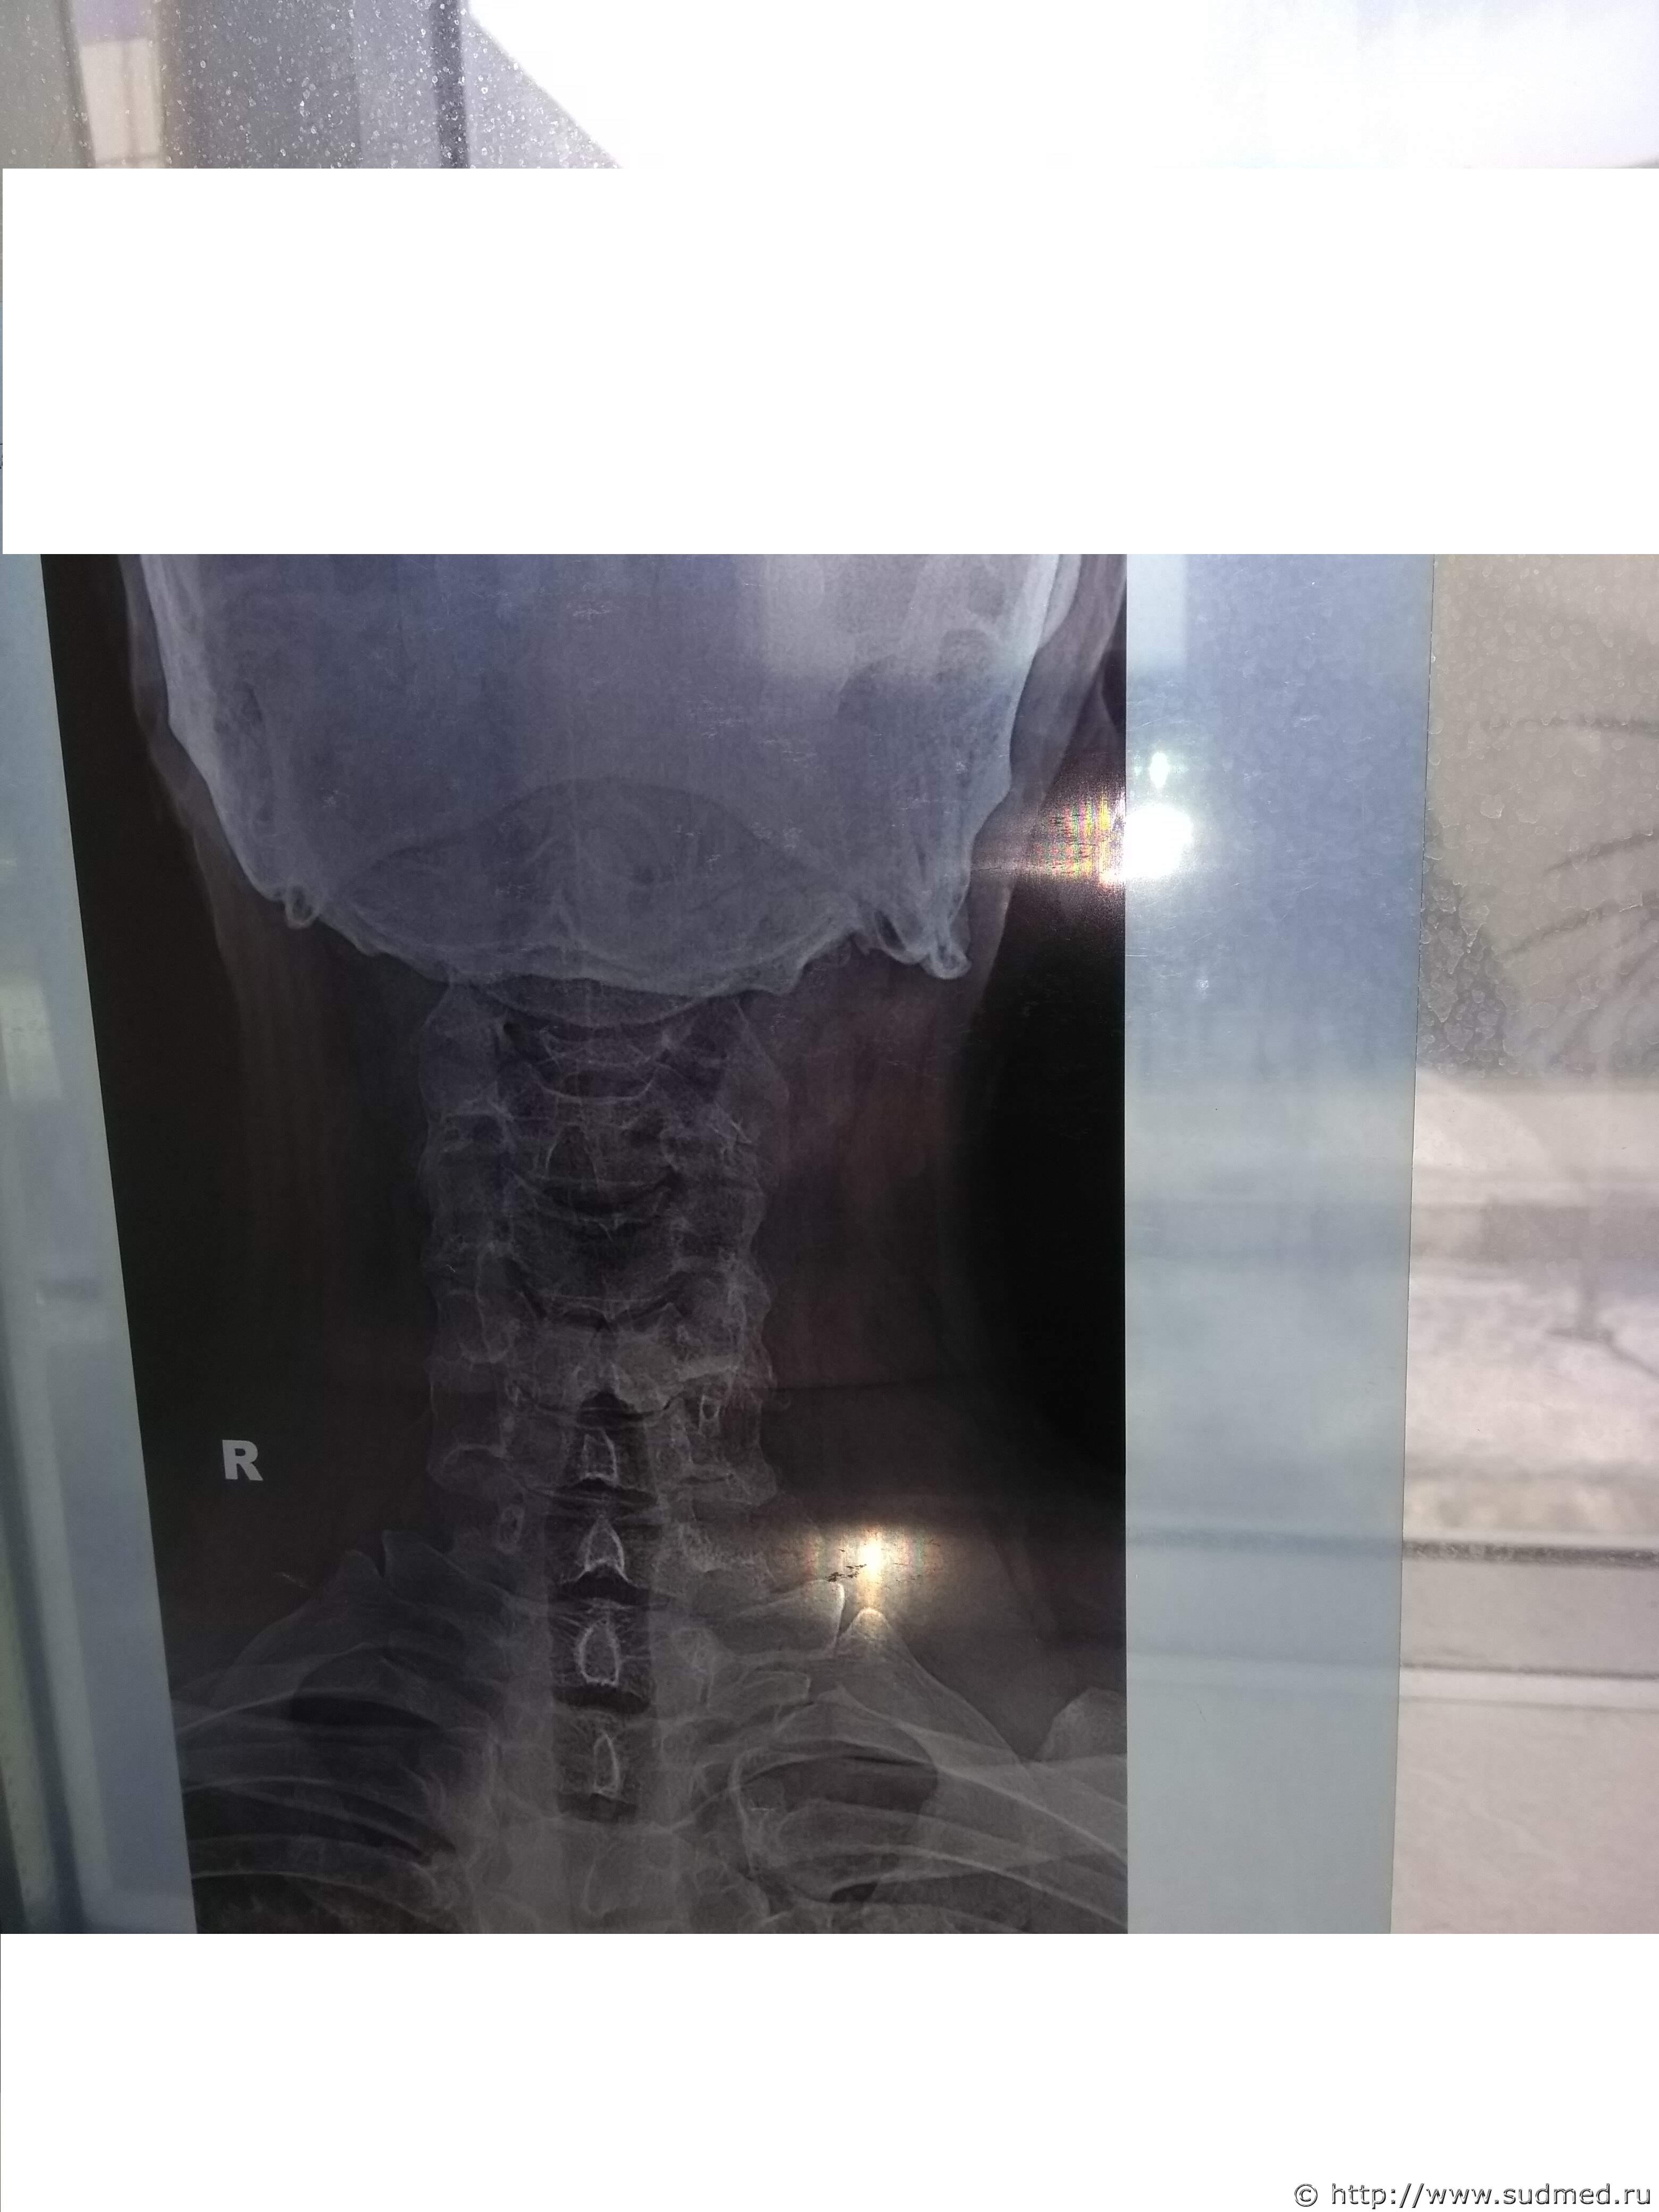

Какие повреждения видны на этой фототаблице?

Похоже на перелом щитовидного хряща, но утверждать не берусь: качество изображений низкое.

А мне кажется там компрессионный 5-6-го, либо перенесенный в анамнезе.